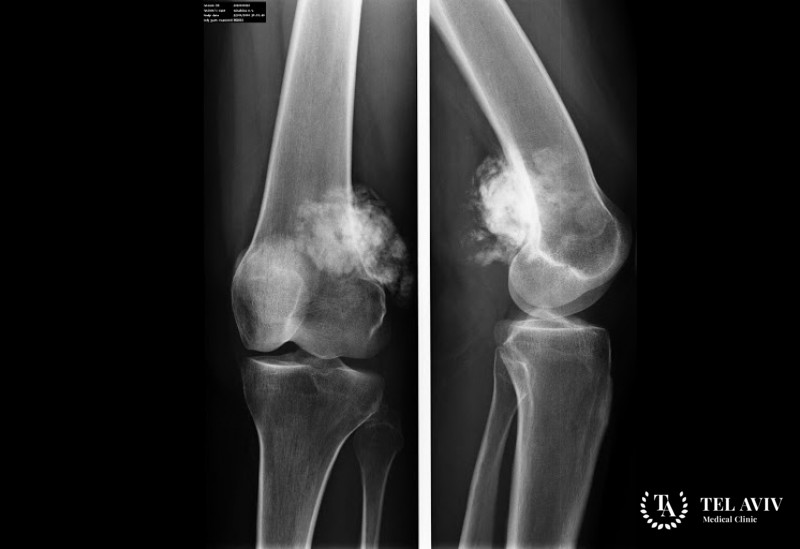

Остеоскаркома – распространенное злокачественное образование, которое состоит из недифференцированной соединительной ткани. Опухоль поражает зачастую верхние и нижние конечности. Заболевание отличается своим агрессивным развитием, метастазированием в соседние органы и прорастанием в структуры. Наиболее часто врачи могут обнаружить патологию у подростков или у людей в возрасте 20-40 лет. При этом мужской пол страдает чаще. К сожалению, обнаружить заболевания на начальной стадии затруднительно. Пациенты воспринимают наличие тупой боли в суставах как воспалительный процесс или последствия после травмы. Однако, если вовремя обратиться к врачу, то прогноз для пациента благоприятный. Заболевание хорошо поддается лечению.

- Рентгенография;